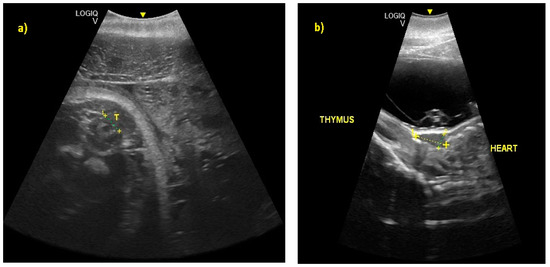

- Ivančič, M.; Gomez, F.M.; Musser, W.B.; Barratclough, A.; Meegan, J.M.; Waitt, S.M.; Llerenas, A.C.; Jensen, E.C.; Smith, C.R. Ultrasonographic findings associated with normal pregnancy and fetal well-being in the bottlenose dolphin (Tursiops truncatus). Vet. Radiol. Ultrasound 2020, 2020, 1–12. [Google Scholar]

- Stone, L.R.; Johnson, R.L.; Sweeney, J.C.; Lewis, M.L. Fetal ultrasonography in dolphins with emphasis on gestational aging. In Zoo and Wild Animal Medicine: Current Therapy 4; Fowler, M.E., Miller., R.E., Eds.; WB Saunders: Philadelphia, PA, USA, 1999; pp. 501–506. [Google Scholar]

- Lacave, G.; Eggermont, M.; Verslycke, T.; Kinoshita, R. Prediction from ultrasonographic measurements of the expected delivery date in two species of bottlenose. Vet. Rec. 2004, 154, 228–233. [Google Scholar] [CrossRef] [PubMed]